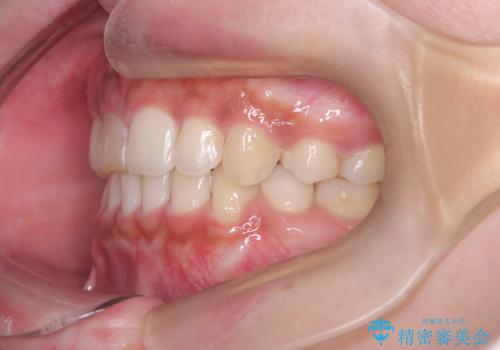

前歯の突出感を改善|上下4本の抜歯と審美ワイヤー矯正でバランスの取れた口元へ

- 患者様は、前歯の突出感を気にされて来院されました。診察の結果、歯列のスペースが不足しており、前歯を後方へ移動させるには抜歯が必要と判断。上下の小臼歯4本を抜歯し、目立ちにくい審美ワイヤー矯正(白いワイヤーと透明ブラケット)を使用して治療を行う計画を立てました。

抜歯によって前歯を下げるためのスペースを確保。その後、審美ワイヤー矯正を用いて、歯列全体のバランスを整えながら前歯を後方へ移動させました。治療後は、横顔のラインが整い、自然な口元になったことで、見た目も噛み合わせも改善しました。患者様からは「口元がすっきりして、自信を持って笑えるようになった」と喜びの声をいただきました。